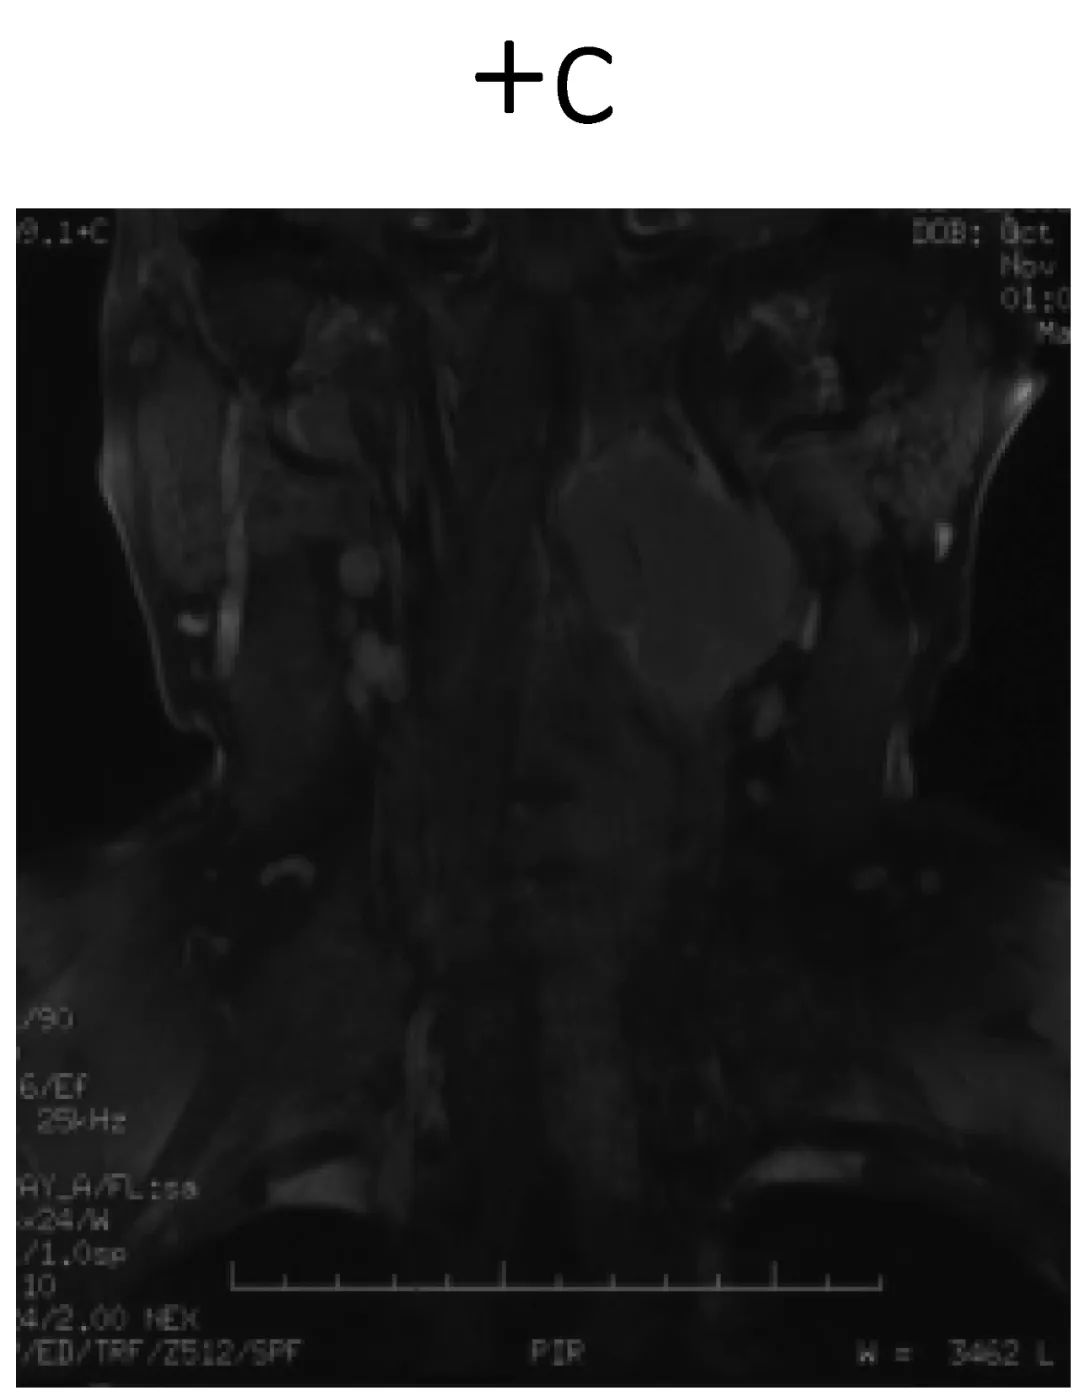

病史:male, 63 y/o

Neck pain for 3 months

影像资料:

诊断:C2椎体肿瘤